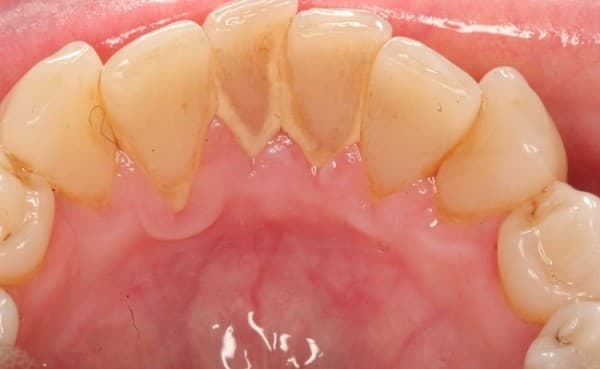

Cao răng là chất cặn cứng có màu vàng nâu, thường đóng xung quanh cổ răng được hình thành từ các thành phần phân hủy của thức ăn, cách chất vô cơ và vi khuẩn trong khoang miệng. Theo đó, cao răng có thể bám trên bề mặt răng, kẽ giữa các răng và ở vùng lợi cổ răng. Một số trường hợp có cao răng dưới lợi gây nên tình trạng tiêu xương ổ răng nghiêm trọng,..

Cao răng bám nhiều trên răng sẽ gây các bệnh lý có hại cho răng miệng, tạo điều kiện cho các vi khuẩn thừa cơ tấn công răng gây nên các bênh răng miệng. Do đó lấy cao răng và đánh bóng răng là việc làm cần thiết thực hiện để chăm sóc tốt sức khỏe răng miệng. Các chuyên gia nha khoa khuyên rằng bạn nên thực hiện khám sức khỏe răng miệng định kì và cạo vôi răng ít nhất 1 – 2 lần trong 1 năm để loại bỏ những vấn đề răng miệng.